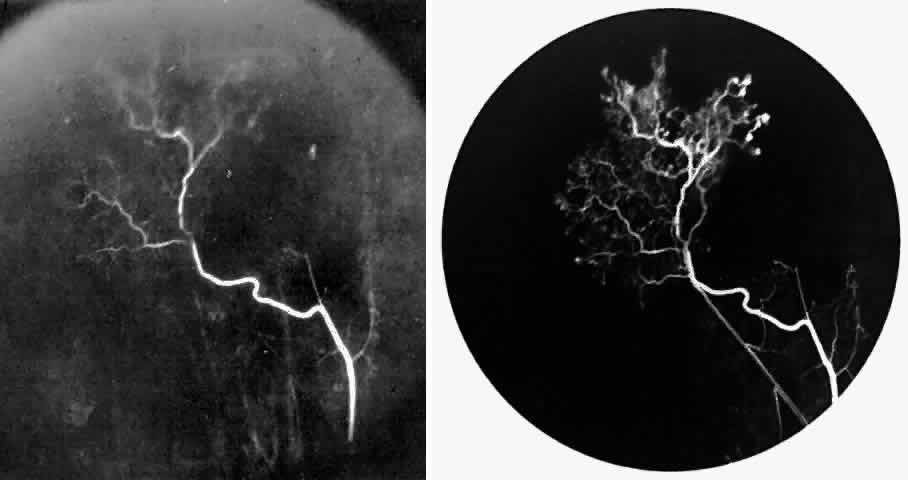

The occluded arterioles may be invisible or may have a “silver-wire” or chalk-white appearance, as first described by Goodman and colleagues39 (Fig. 21). Fluorescein angiography may demonstrate an abrupt complete occlusion at the interface between peripheral nonperfused and posterior perfused retina. Frequently, this occlusion will take place just distal to a branching vessel, giving the appearance of a freshly pruned rose bush. The nonperfused anterior peripheral retina will have a grayish brown appearance and on fluorescein angiography will appear blurred without clearly defined fundus markings.

Fig. 21. A. Photograph of the peripheral retinal vasculature shows sheathed vessels and absence of peripheral vascular perfusion. B. Fluorescein angiogram shows area of nonperfusion representing stage I sickle cell retinopathy. White arrow points to corresponding vascular bifurcation in A and B.